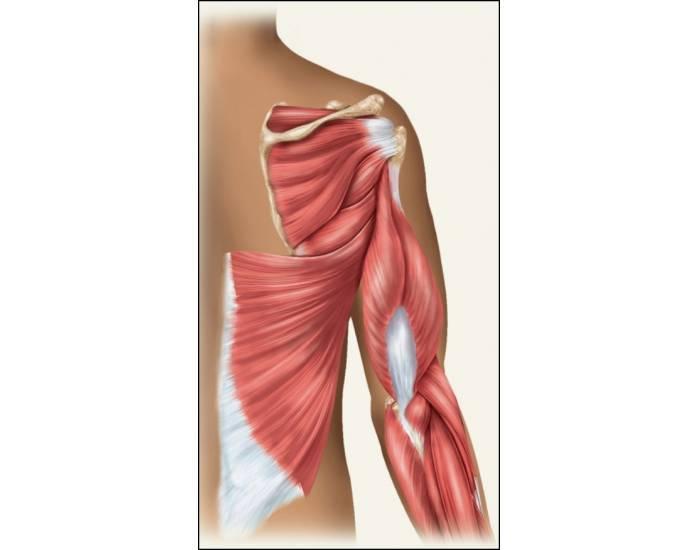

LES RAPPORTS ANATOMIQUES AU NIVEAU DU BRAS

- L’artère brachiale chemine dans le canal brachial de Cruveilhier

- Le canal brachial est constituer par l’aponévrose brachiale, les muscles coraco-brachial, le biceps brachial et le brachial antérieur, ainsi que le septum intermusculaire médial

LES RAPPORTS AVEC LES PAROIS

– Traversant la partie médial du bras

L’artère brachiale affecte des rapports avec les parois de la loge brachial

Le biceps brachial et le brachial antérieur en avant et en dehors

Le sillon intermusculaire et le triceps brachial en arrière

Le caraco-brachial en dedans

L’aponévrose brachial et les plans sous-cutanée en dehors

RAPPORTS DORSALES

Représenter par la paroi postérieur qui comprend:

- Le muscle triceps brachial

- La cloison intermusculaire

Représenter par la paroi ventrale du bras qui comprend:

- Le muscle brachial antérieur

- Le muscle coraco-biceps

RAPPORTS VENTRALES

Représenter par la paroi ventrale qui comprend:

- Le muscle biceps brachial

- Les plans aponévrotiques et cutanées